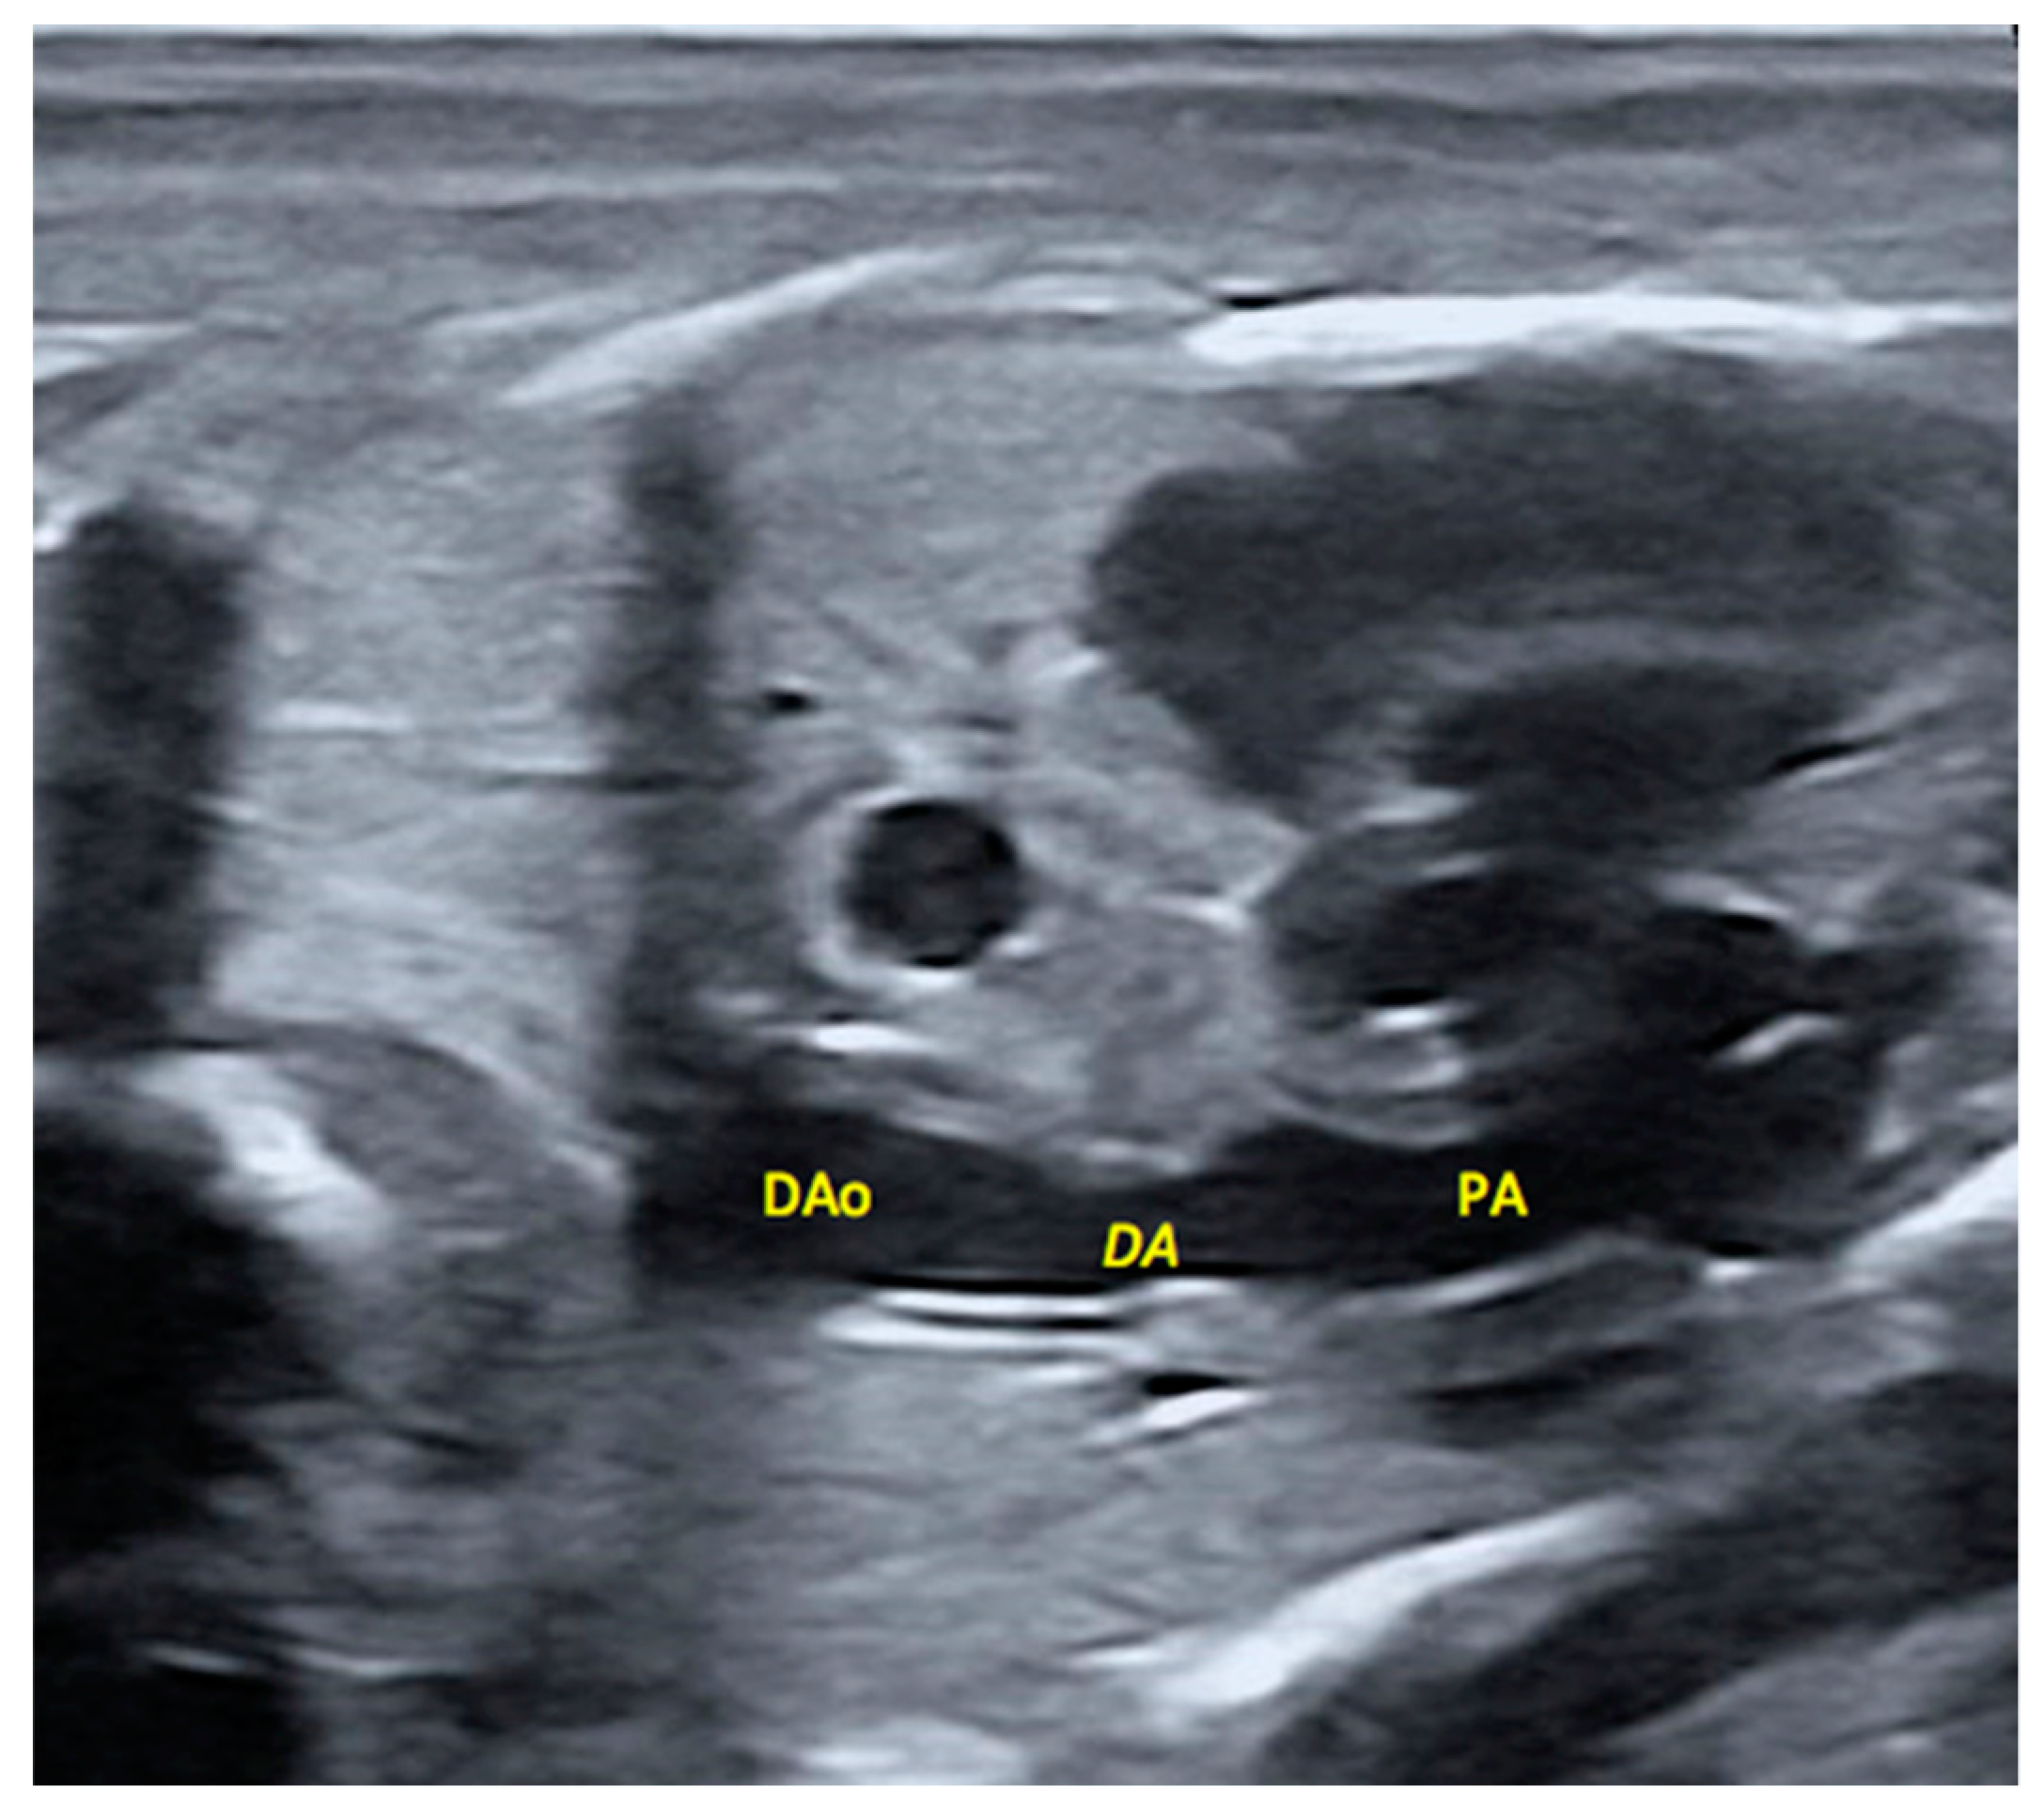

2.5. Morphological Appearance of Fetal Descending Aorta and Ductus Arteriosus